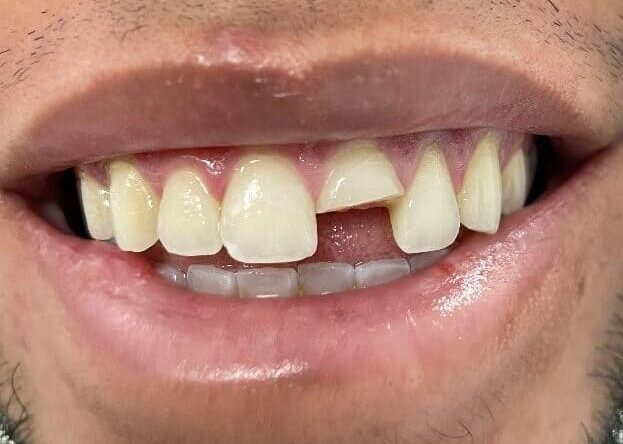

When Tooth decay extends deep under the gum, the tooth is cracked, severe periodontal disease is present, or a tooth infection cannot be resolved a tooth extraction is recommended as the best option.  Tooth pain caused by a broken or infected tooth is a dental emergency which may require a tooth extraction to resolve.

Tooth extraction for a cracked tooth

Not all Cracked or fractured teeth require to be extracted.  At Smile Arts of NY we can save teeth that maybe fractured or broken.  Our dentist will carefully evaluate the condition of your tooth or teeth.   Many fractured teeth can be saved with a crown or a filling.  We may have to do a little work on your gums with our small diode laser. if the tooth fractured under your gum.  A root canal maybe necessary if there’s nerve damage to the tooth.